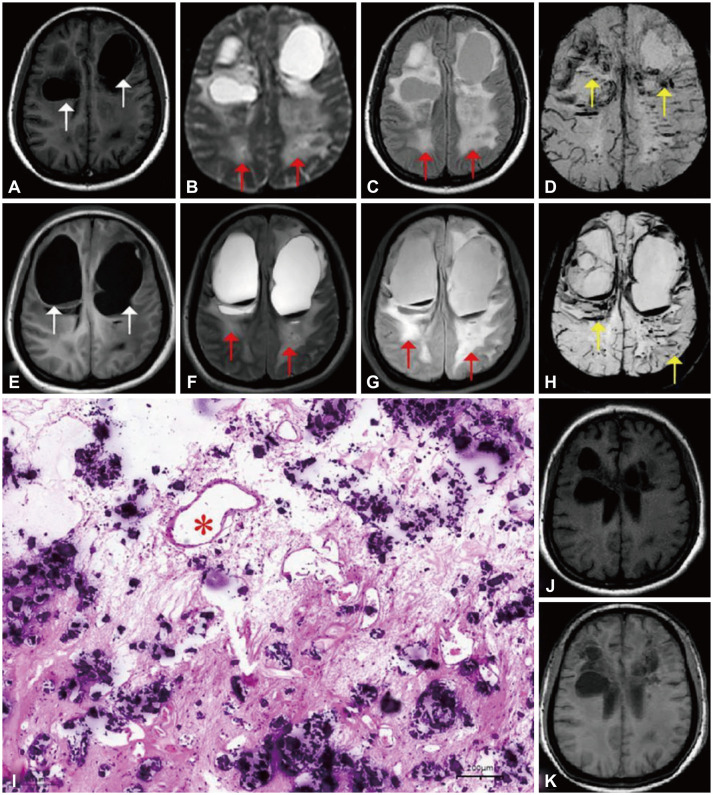

伴有脑钙化和囊肿的脑白质病伴新的SNORD118突变,表现为双侧巨大囊肿。

Leukoencephalopathy With Cerebral Calcifications and Cysts With Novel <i>SNORD118</i> Mutations Presenting With Bilateral Giant Cysts.

Leukoencephalopathy With Cerebral Calcifications and Cysts With Novel SNORD118 Mutations Presenting With Bilateral Giant Cysts.